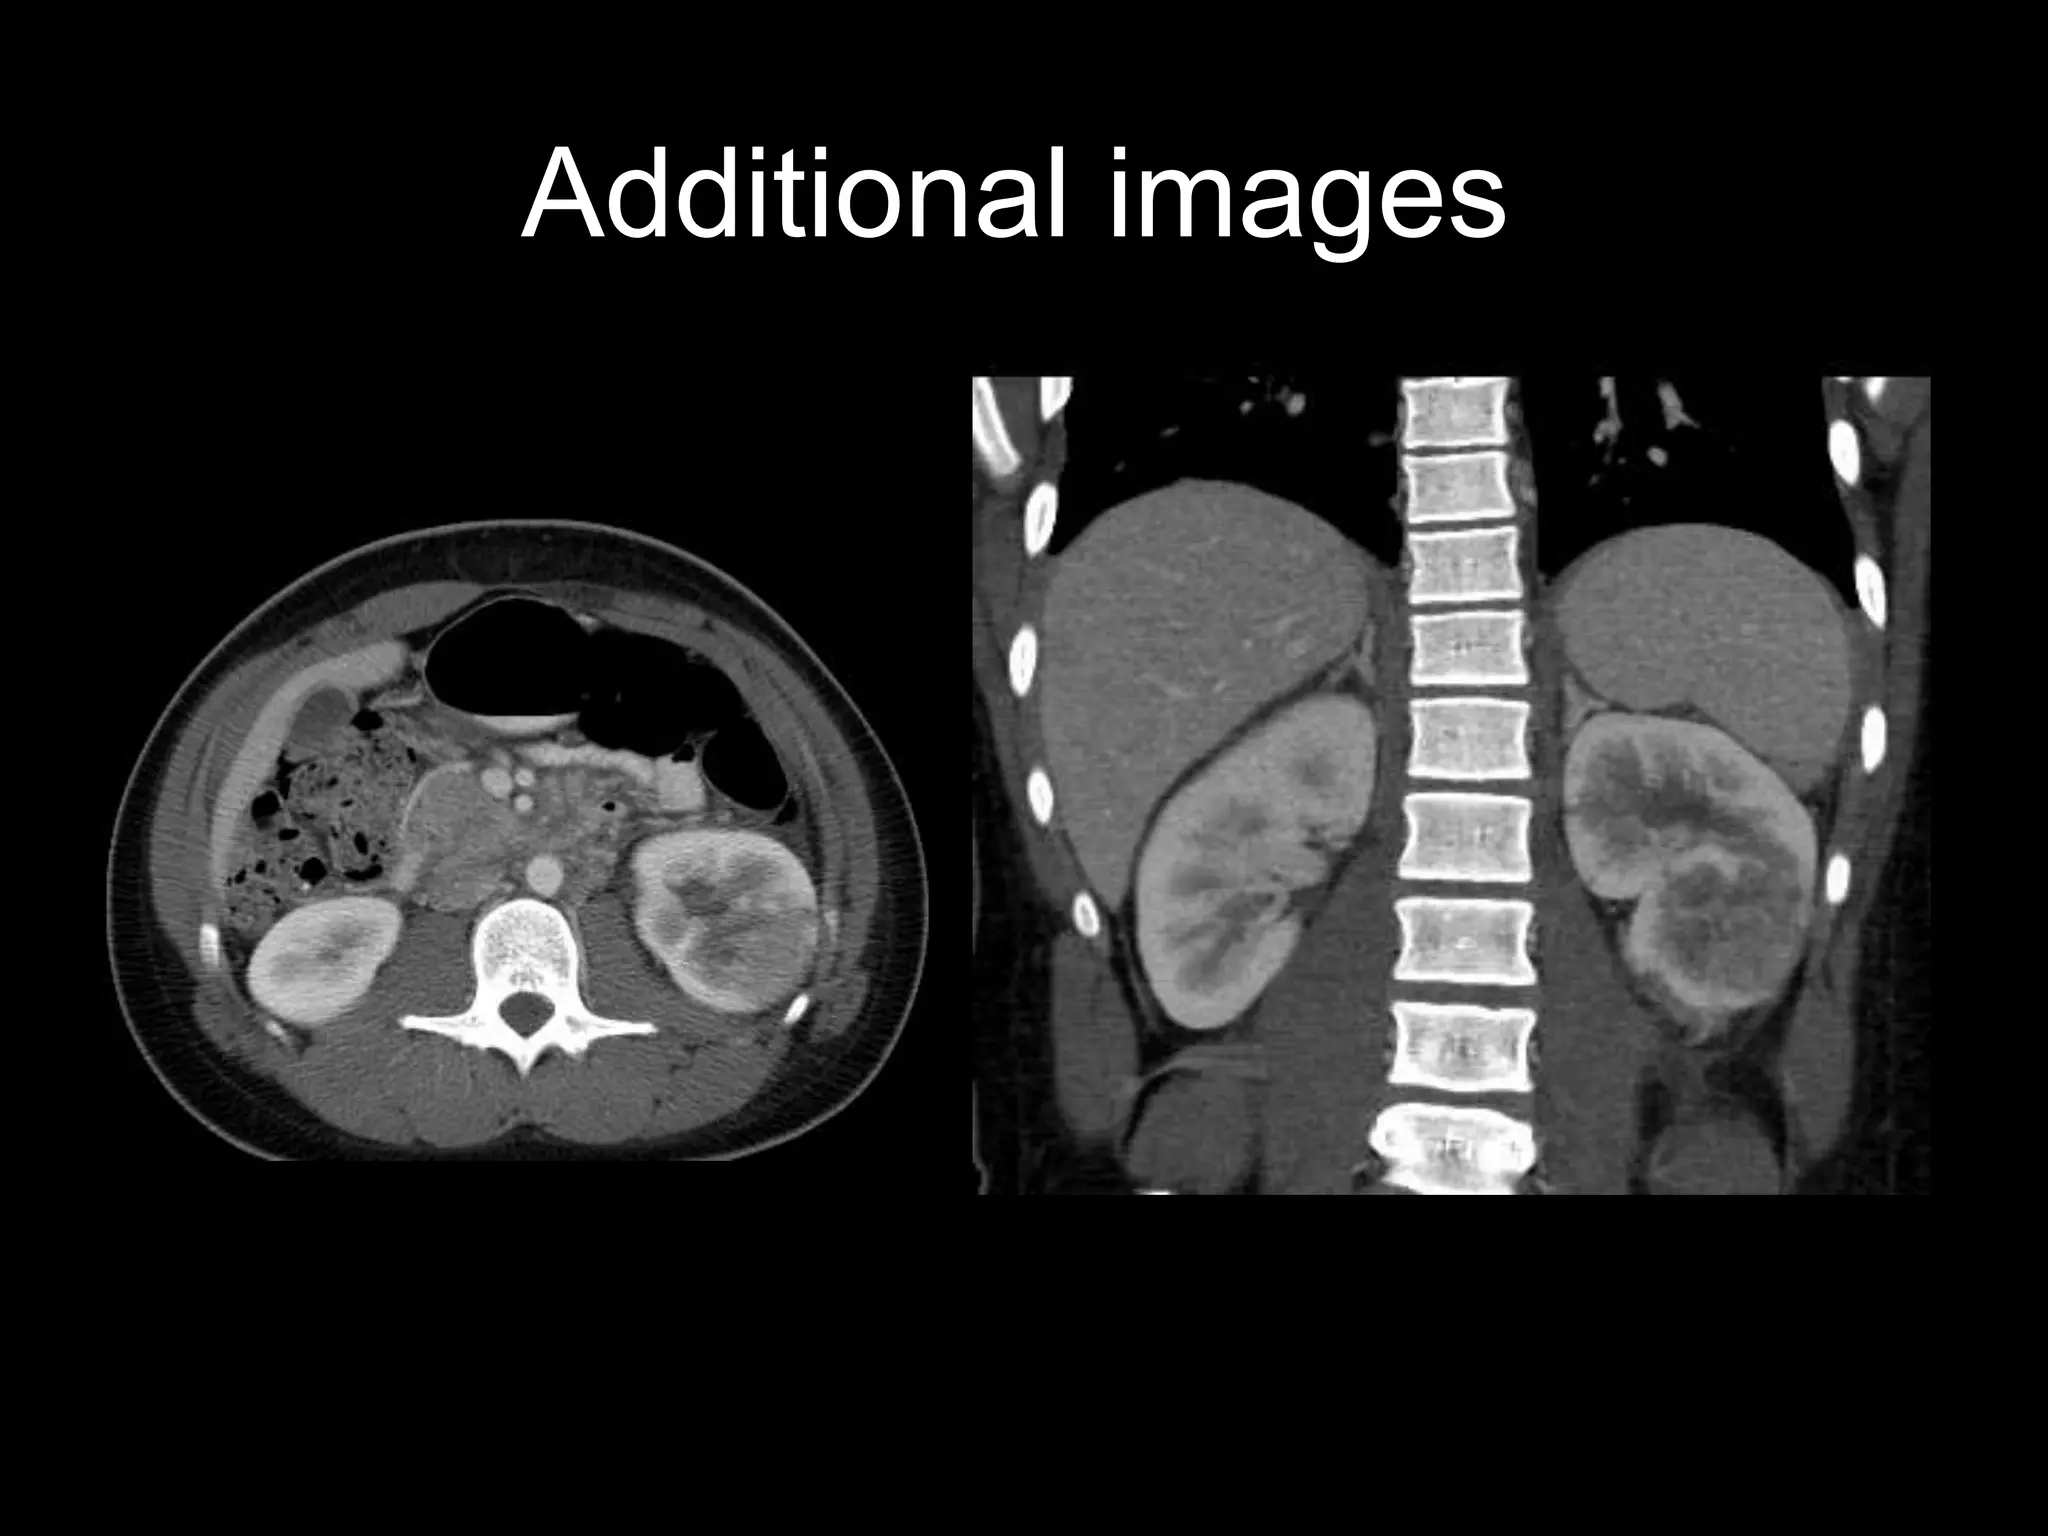

15 y.o. African American male with cough, shortness of breath, 10 # weight loss

Additional images

Findings

• CXR – interstitial, septal

thickening

• Chest CT – septal

thickening, multiple small

nodules, ground glass opacities

• Abdominal CT –

infiltrative, indistinct left renal

mass

Pulmonary lymphangitic metastases

Metastatic renal medullary carcinoma

• Demographics:

– Seen almost exclusively in pts with sickle trait

– Age range = 11 – 39, Male: female=3:1

• Symptoms: pain, hematuria, wt loss

• Renal mass imaging features

– Infiltrative, associated necrosis, caliectasis

– More commonly right-sided

• Often widely metastatic at dx

– Pulm lymph spread is common